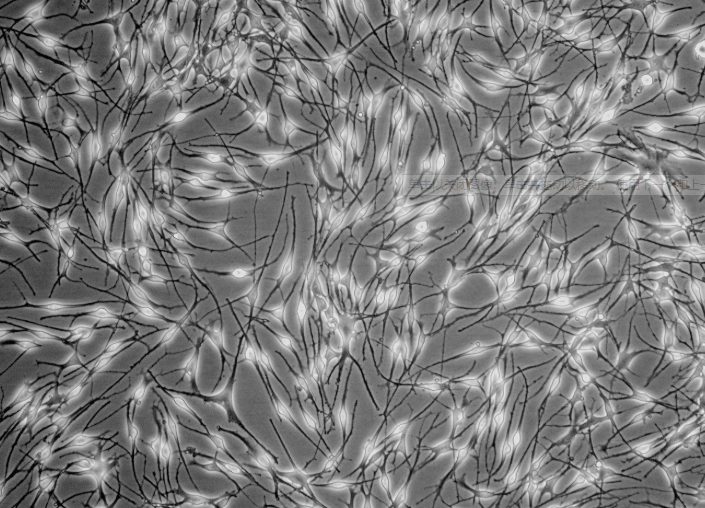

生长特性:贴壁细胞

细胞形态:上皮细胞样

背景描述:SK-N-SH人神经母细胞瘤(通过STR鉴定)是由J·L·Bieder建系,它与SK-N-MC细胞所不同的是倍增时间较长,且多巴胺-β-羟基酶水平较高。SK-N-SH细胞在细胞介导的细胞毒性试验中用作靶细胞系。